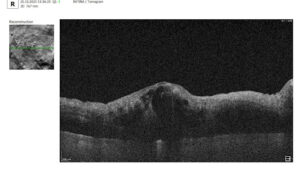

In contrast, macular OCT scans (Figure 3) focus on the central retina, providing detailed visualization of structures such as the foveal center, retinal layers, and macular biomarkers (such as drusen, hypertransmission, fluids etc). Since the macula is anatomically distinct from the optic nerve head, standard macular scans do not capture the ONH comprehensively.

Figure 3. 6 mm OCT b-scan of the macular region, showing the foveal pit and retinal layers.